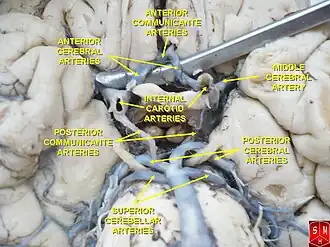

The internal carotid then divides to form the anterior cerebral artery and middle cerebral artery. The circle of Willis provides a collateral pathway for blood supply to the brain.

Circle of Willis

Circle of Willis -

Diagram of the arterial circulation at the base of the brain (inferior view).

Diagram of the arterial circulation at the base of the brain (inferior view).